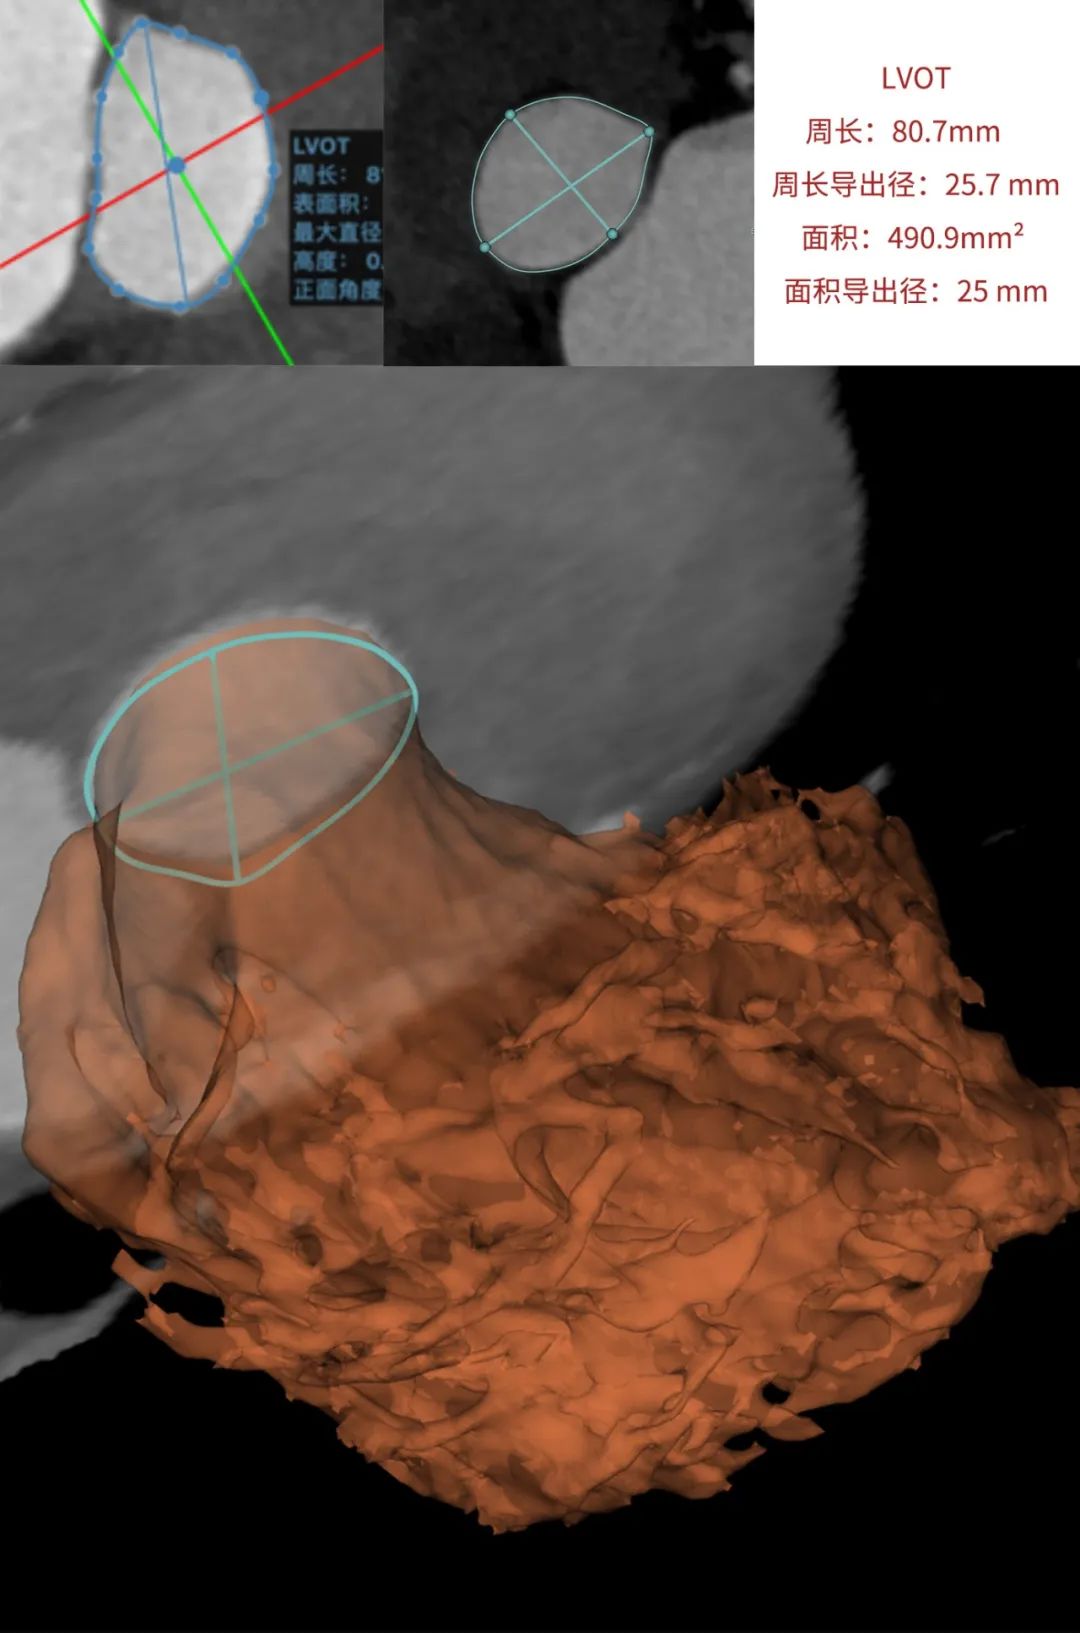

患者为68岁男性,因心悸胸闷入院。术前超声报告显示,患者为功能型二叶式主动脉瓣,右无融合钙化,主动脉瓣明显增厚钙化,瓣叶开放受限,主动脉瓣前向血流加速Vmax=4.2m/s,平均跨瓣压差36mmHg,有效开口面积0.7cm²,舒张期瓣口中度反流信号。

临床团队同时使用了基于医生手工描点的围术期影像评估软件和基于人工智能的瓣膜疾病围术期分析辅助决策软件进行术前影像学评估。

通过术前测量,对病例深入分析,结合人工智能术前分析辅助决策软件进行三维和二维图像融合,郭应强教授指出本例手术存在以下难点:

瓣叶明显增厚钙化,瓣膜释放过程中存在移位风险。

功能型二叶式主动脉瓣,瓣叶开口偏向一侧,瓣膜释放后存在不同轴可能。